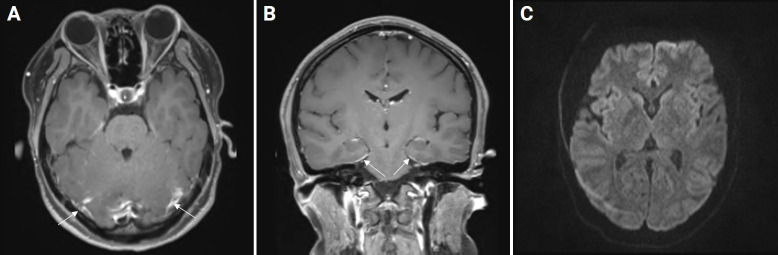

Tuberculous meningitis (TBM) is fatal unless treated promptly. Nonconvulsive status epilepticus (NCSE) may cause altered consciousness in patients with TBM. A 25-year-old female presented to the emergency department with a headache and fever along with multiple associated symptoms that had developed 2 days prior. Based on clinical findings, brain imaging, and cerebrospinal fluid (CSF) examination, she was tentatively diagnosed with viral meningitis. Later, she developed altered consciousness with focal seizures, and follow-up CSF examination findings and electroencephalography were consistent with NCSE complicated by TBM. We encountered a patient with TBM who exhibited initial atypical CSF findings and NCSE, and we report the case here and discuss the pathomechanisms.